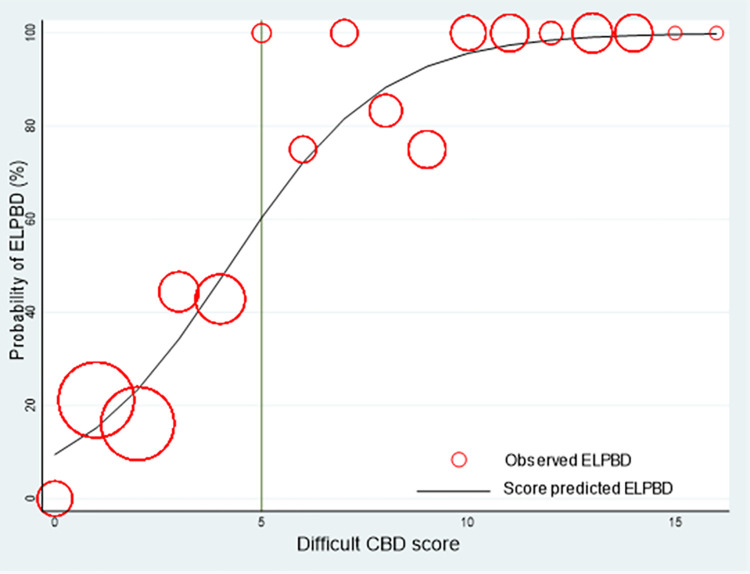

Score transformation

Each predictor’s regression coefficient was used as a weight for score transformation, and the results are presented in Table 3. As demonstrated in Table 3, the scores ranged from 0 to 16, classifying patients into two difficult groups at a cutoff of 5 points. The score for the non-difficult group was 0 to 4 for low-requirement EPLBD, whereas the score for the difficult group was 5 to 16 for high-requirement EPLBD.

A calibration plot revealed that the score predicted the probability of EPLBD requirement, and the observed risk of EPLBD requirement in the derivation cohort concomitantly increased as the score increased (Fig 3). We selected a cut point value at 5 because of high specificity (94.74%) and sensitivity (72.15%), allowing for the inclusion of individuals with more difficult CBD stones. A score of 5 or higher will likely require EPLBD or further procedures. It was suggested that patients should be referred to a hospital with the necessary equipment to dilate CBD or to make the stones smaller. (Fig 4).